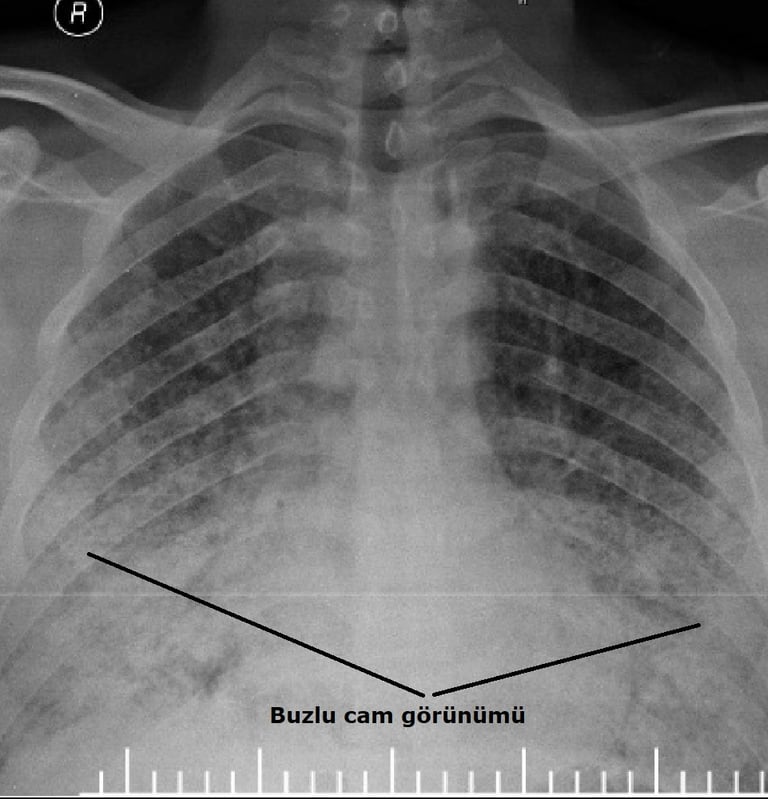

Bilateral Periferik Buzlu Cam Görünümü (GGO): Alveoler boşlukların proteinöz eksüda, hiyalin membranlar ve inflamatuar hücrelerle kısmen dolması. LR+ 4.8 Skor: +4 Puan